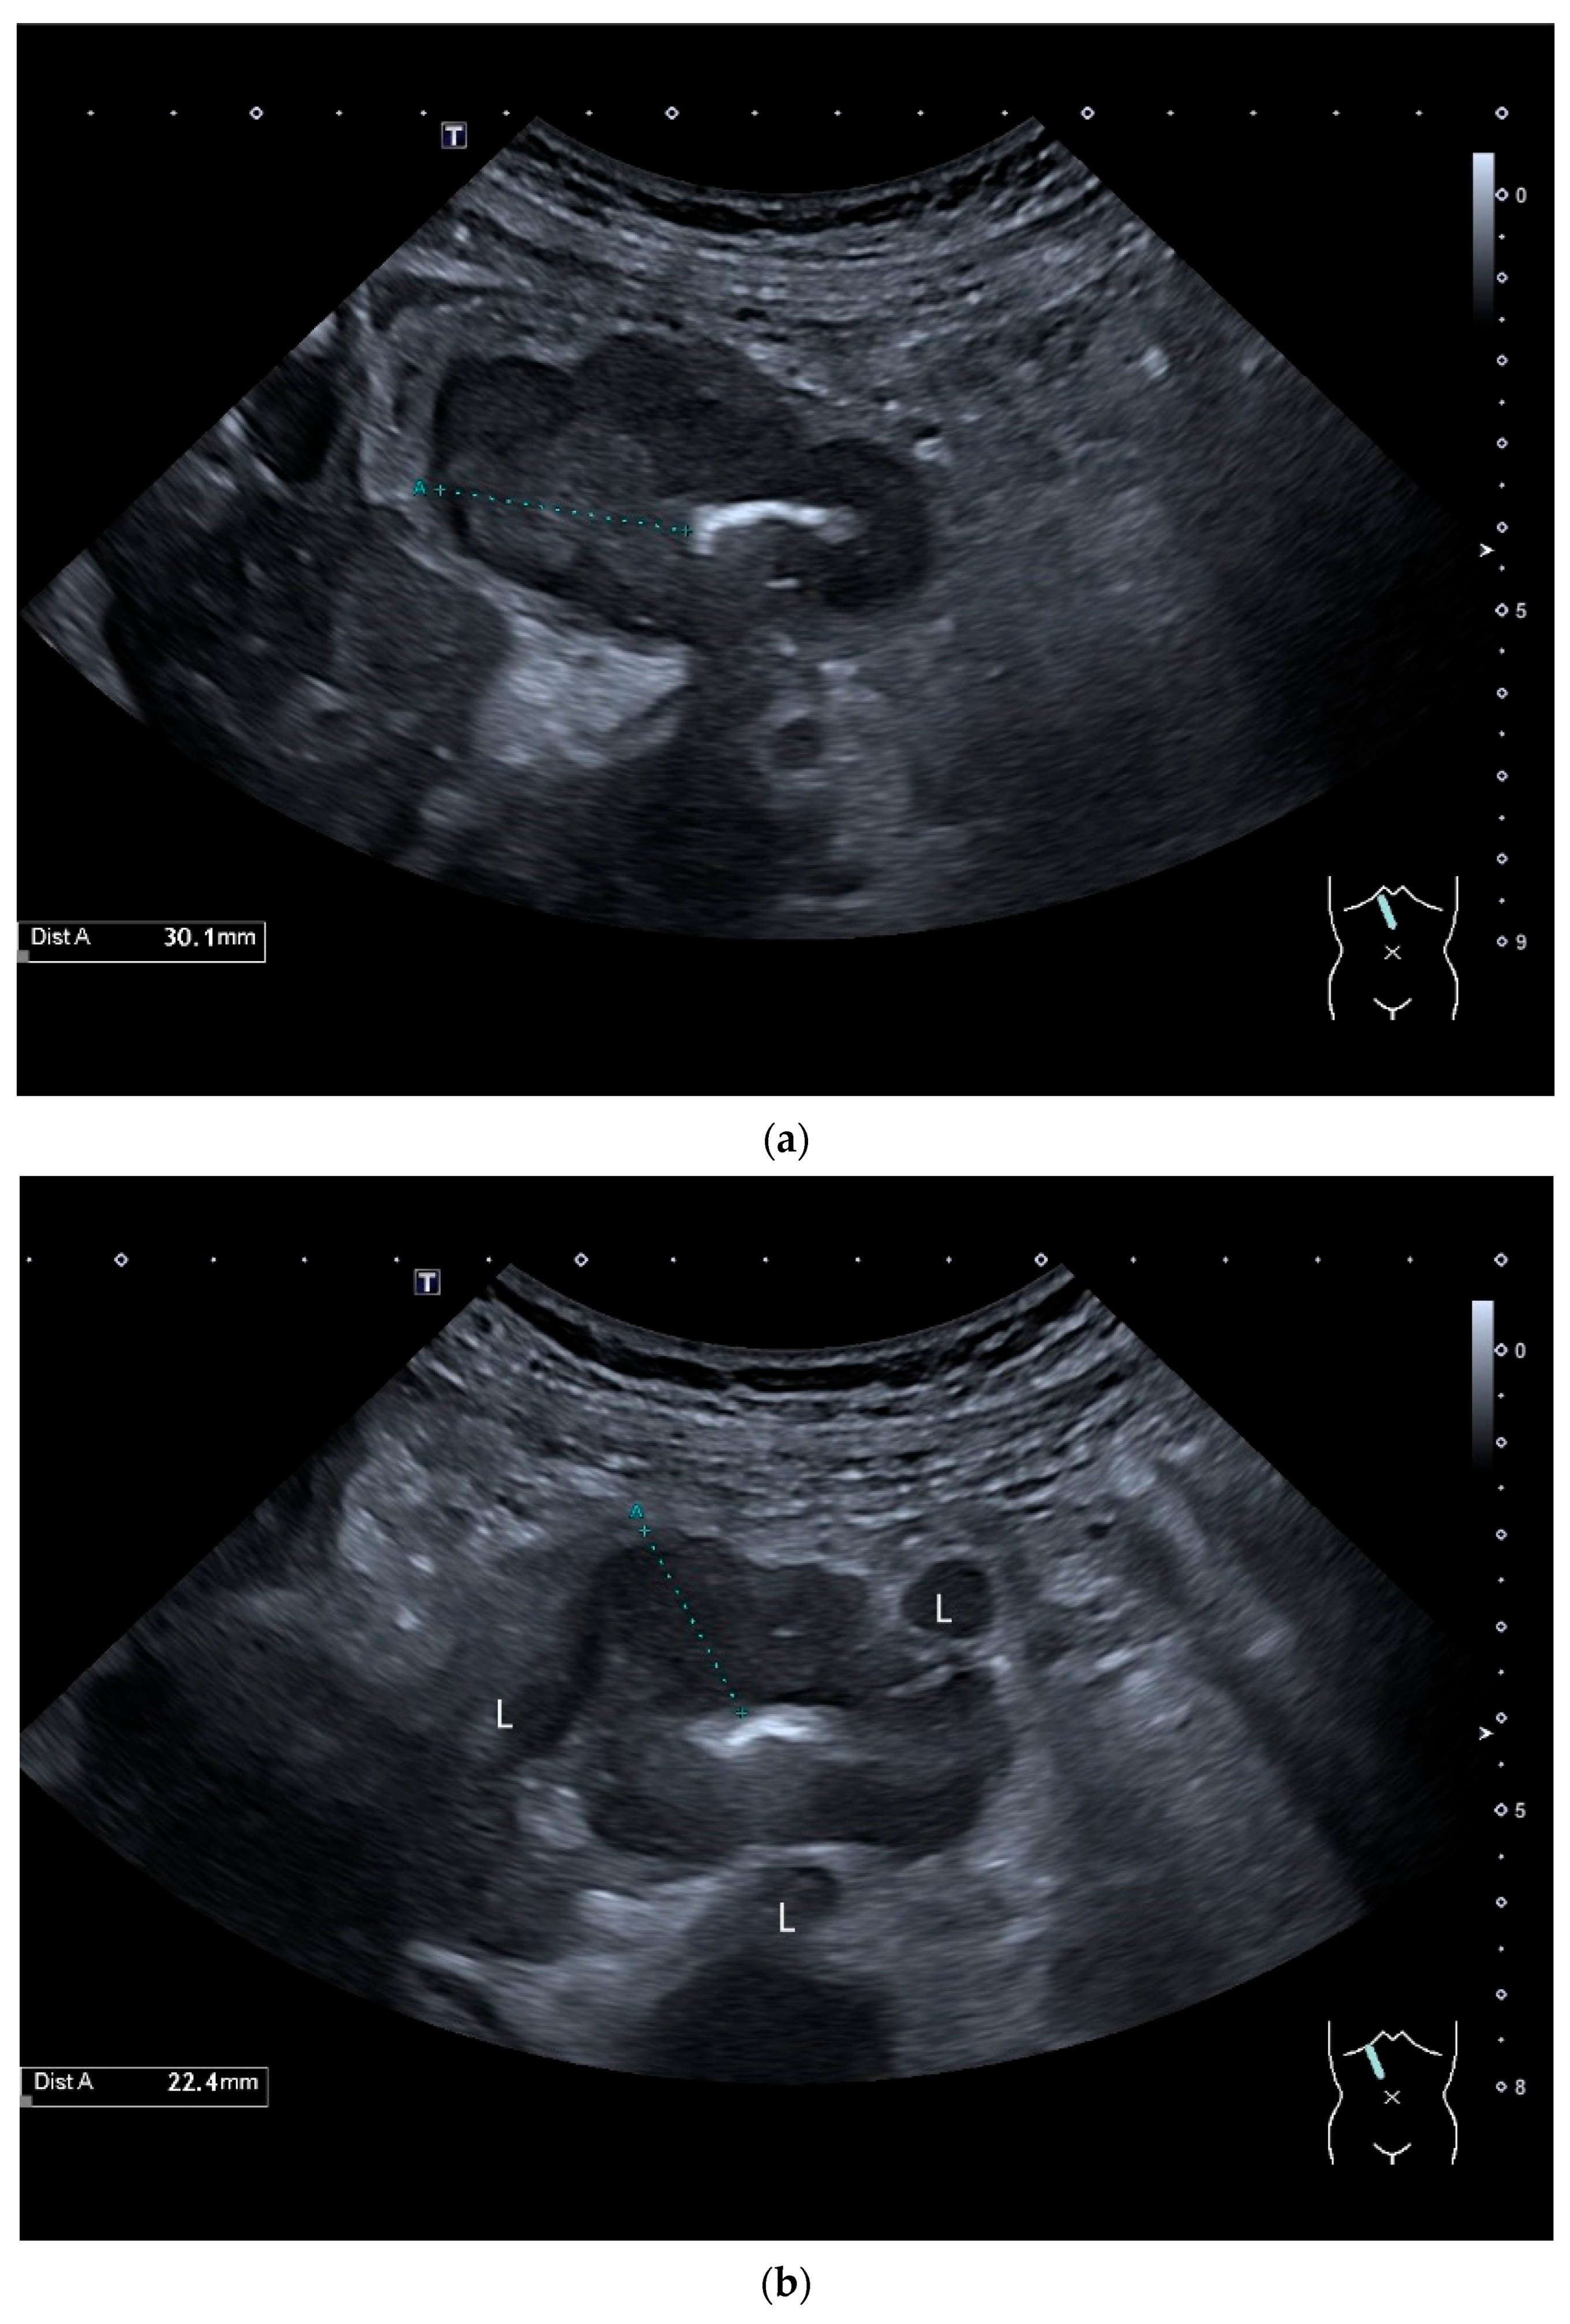

Precise descriptions of subepithelial intramural masses including GIST are known from endoscopic ultrasound (EUS) [128]. Despite the lower resolution and proximity, the findings known from EUS can generally be transferred to US. However, in the small intestine, it is much more difficult to classify the layers, as the healthy wall is only up to 2 mm thick. GIST can develop into the lumen of the gastrointestinal tract or be located extraluminally. On EUS as well as on US, small GIST are generally round, homogeneous, and hypoechoic compared to submucosal layer, but isoechoic to the Lamina muscularis propria. On CDI, they show macrovessels. Larger GIST may be lobulated and heterogeneous, show necroses as hypoechoic or nonechoic liquid areas as well as calcifications. Air inclusions in the tumor are an indication of deep ulceration of the tumor surface with central necrosis and connection to the gastrointestinal tract lumen [55] (Figure 11 and Figure 12).

Figure 11.

GIST. A 30 mm large, very hypoechoic, almost anechoic round mass is visible in the left upper abdomen. This is located in the jejunum; the wall (W) and lumen (L) are visible (a). Macro vessels can be distinguished on Power Doppler, demonstrating that the lesion is solid and not cystic (b). On CEUS with 2.4 mL SonoVue (linear transducer 9 MHz), a small wheel-spoke-like vascular branching is visible at the margin (arrow) (c) with centrifugal enhancement (arrow) (d). Hyperenhancement is heterogeneous in the early arterial phase (e,f) and becomes homogeneous in the later course of the arterial phase (g). The extent of the heterogeneously enhanced tumor is marked with arrows (e). The intensity of the enhancement decreases during the first minute. The tumor is marked with arrows (h). Jejunal segment resection revealed the histology of an epithelioid GIST.

Figure 12.

GIST. Incidental finding of a 35 mm, slightly polycyclic, homogeneous hypoechoic mass in the left upper abdomen (a,b). This changes position with the movements of the small intestine. In CEUS with 1.2 mL SonoVue using the abdominal sector transducer (1–5 MHz), the mass shows homogeneous hyperenhancement in the arterial phase (c). The intensity then decreases (d). The tumor is marked with arrows in CEUS.